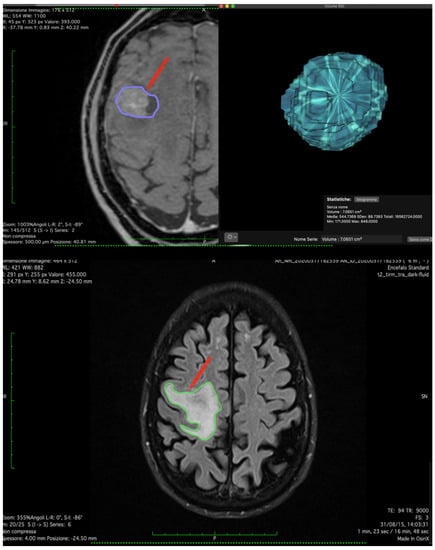

| Volume (cm3) | 14.62 ± 18.5 |

| Edema Volume (cm3) | 54.21 ± 45.76 |